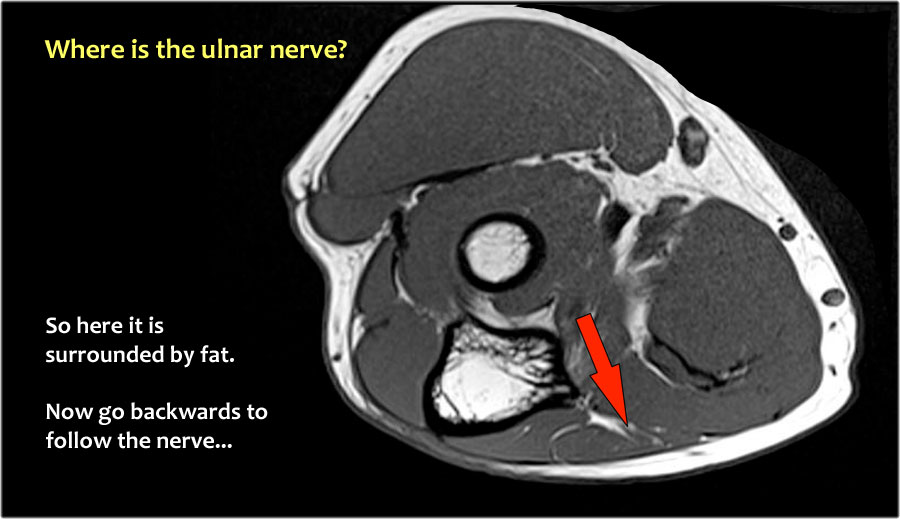

Một cách để thực hiện là đi theo các cấu trúc về phía xa cho đến khi tìm thấy dây thần kinh trụ ở phía xa tại vị trí bình thường của nó ở vùng cẳng tay gần được bao quanh bởi mô mỡ.

Sau đó khi bạn theo dõi nó về phía gần, bạn sẽ nhận thấy rằng đây là một trường hợp chuyển vị dưới da.